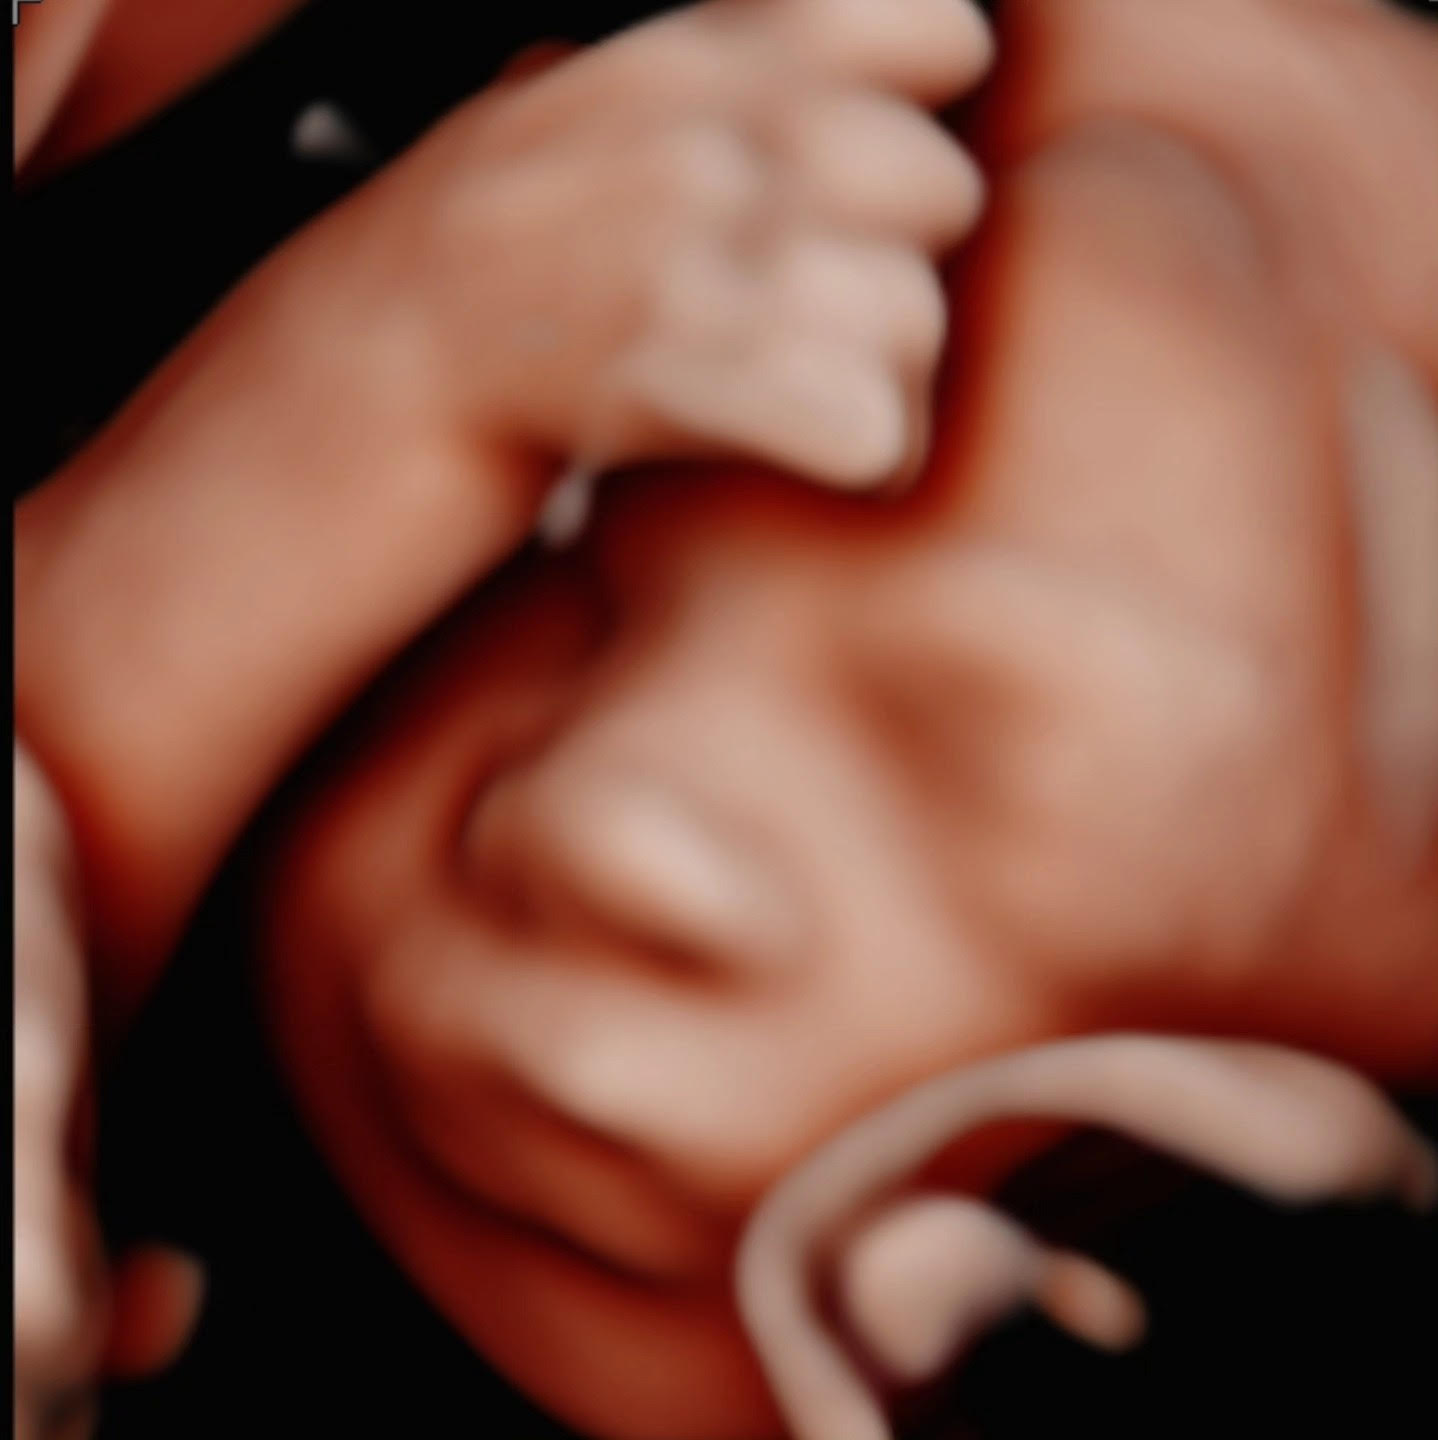

Browsing our 4D ultrasound photos gives you a clear idea of what your session can look like. You will see a range of images, from early 2D visits and gender reveal moments to rich 3D, 4D, and HD live facial detail captured during the most popular weeks between 26 and 32 weeks. Babies are unpredictable, but we have spent many sessions helping families get those sweet expressions, tiny stretched arms, and peaceful faces that you will want to hold onto for years.

Our experienced team guides you through every part of the visit. When baby needs encouragement to move into a better position, we walk you through simple techniques that can help. We never rush through the session looking for a quick shot. We take time, adjust angles, and work patiently to find those moments that matter most.

Hydration is one of the most helpful things you can do before your visit. Staying well hydrated in the days leading up to your appointment supports clearer amniotic fluid, which directly affects image quality. Drink plenty of water starting several days before you come in.